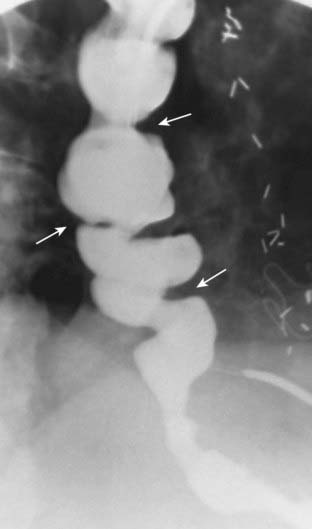

image

Figure 18-17 Villous tumor of cecum.

There is a large, polypoid mass in the cecum (outlined by both black and white solid arrows). Contained within the mass is an interlacing network of white lines representing barium that is trapped within the interstices of the frondlike projections from this tumor. This is a characteristic appearance for a villous adenomatous tumor.